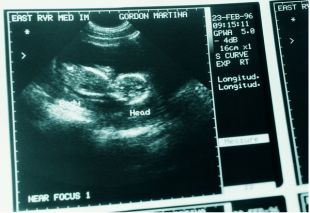

大家请看如上的这张图,就能大概感知胎盘前壁是在哪个位置。胎盘前壁意味着子宫的上段对着孕妇肚皮的下方,因为胎盘更靠近肚子,孕妈的的肚子会比较突出,即平常所说的显怀,一般会比同月份的孕妈肚子略大一些。